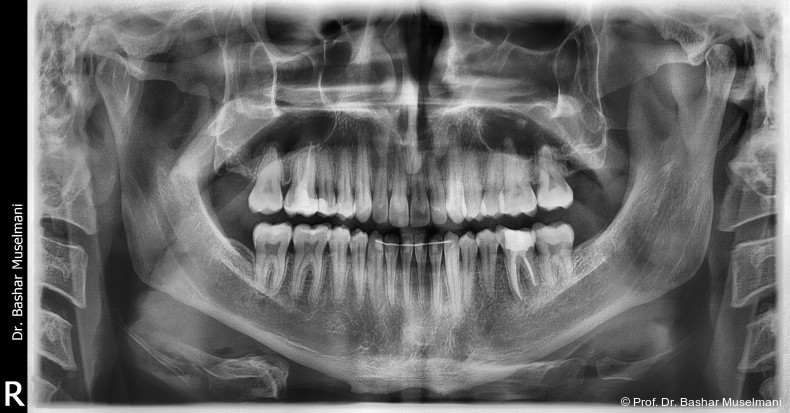

Der Patient (28 Jahre 8 Monate) stellte sich mit einer skelettalen Klasse III sowie einer Mittellinienabweichung nach links vor.

Fernröntgenologische Befunde (Behandlungsbeginn)

• SNA: 81,5°

• SNB: 84,3°

• ANB: −4,9°

• Wits-Wert: −8,4 mm

Die Abbildungen 1 bis 3 zeigen die initiale klinische und radiologische Ausgangssituation.

Während des Behandlungsverlaufs wurden ein Kontroll-Fernröntgenseitenbild sowie ein Orthopantomogramm angefertigt.